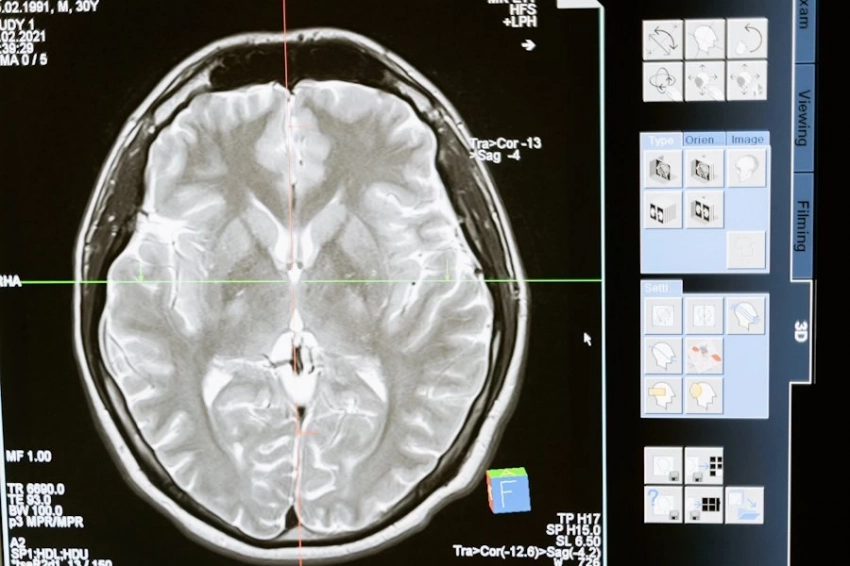

По версии Оксфордского университета, словом года назван «сгнивший мозг». Американский нейробиолог пояснил, что означает термин, и почему выбран именно он, в интервью телеканалу Fox News

Регулярный просмотр подобных роликов активирует хабенулу. Эта область в человеческом мозге ответственна за чувство удовлетворения и мотивацию. Ученые в ходе эксперимента выяснили, что хабенула может порой отключать способность человека к самоконтролю. И пользователь начинает бесконечно пролистывать ленту, возникает своего рода зависимость от TikTok и схожих платформ.

Это негативно отражается на памяти. Пользователи обычно не могут вспомнить, о чем смотрели ролик минуту назад. Есть и психологические последствия. Нарастают негативные эмоции, в первую очередь, развивается тревожность и чувство вины. А дальше человек попадает в замкнутый круг, поскольку негатив активирует хабенулу ещё сильнее. Кроме проблем с памятью, происходит потеря концентрация и воли к жизни. Таким образом мозг «загнивает».